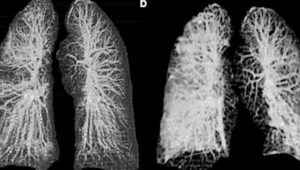

Así lucen los pulmones de personas con Coronavirus a través de los rayos X

Médicos italianos dieron a conocer como es que lucen los pulmones de dos personas infectadas por el Covod-19.

Las radiografías y tomografías muestran los órganos visiblemente deteriorados, en particular, se puede observar cómo el virus reduce el espacio funcional de los pulmones, ocasionando problemas para respirara.

Según la investigación, la infección hace que los espacios cruciales para el aire se llenen de pus, sangre o agua.

Los autores del estudio señalaron que al momento de publicar las imágenes, ambos pacientes se encontraban en condición crítica pero estable.